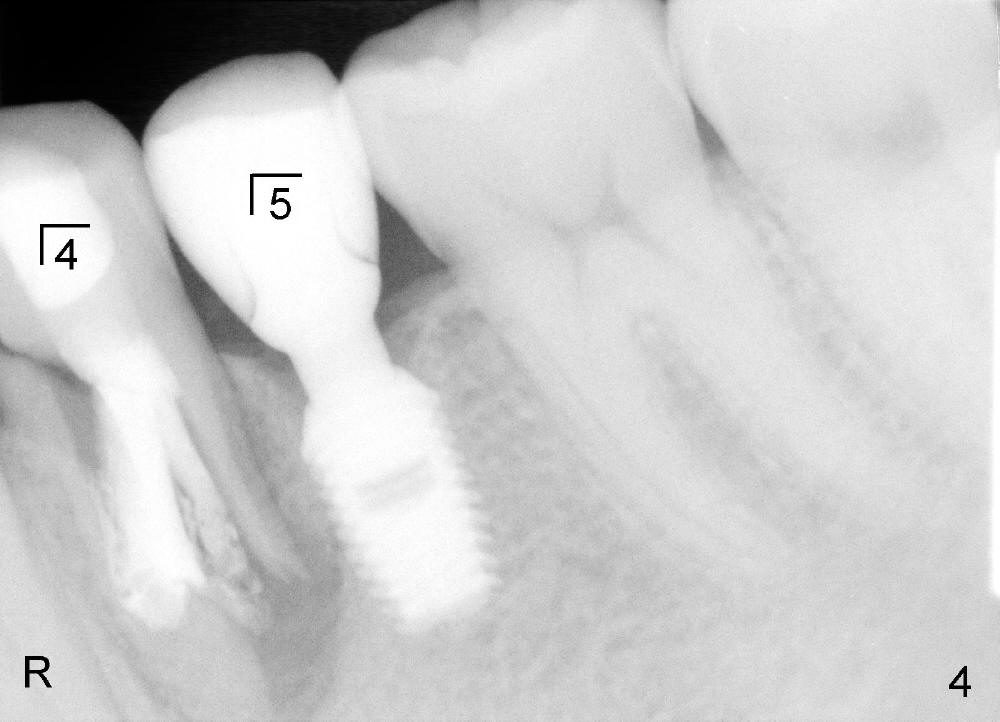

昨天(治疗后五年)左下第一双尖牙根部红肿(图三*),根尖片显示根裂(图四),阴影累及第二双尖牙植牙和尖牙根部(R)。由于发现突然,病人和家属不同意立即治疗,他们要等到病人下次放假才接受治疗,而我们心急如火,害怕炎症破坏植牙。如果条件允许的话,拔牙后即刻植牙(直径大些,长些,补偿巨大骨质缺损),目前抗菌素治疗,最好拔牙前再使用抗菌素一到两天。

尽管Bicon植牙短,但是还能接受考验。中央牙尖牙齿牙冠部分没有什么缺损,根管治疗后不必做牙冠,这种牙齿虚弱之处是牙根,再次根管治疗促进根裂,当时想减少植牙周围感染。